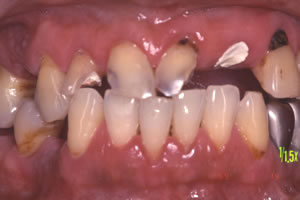

症例3![]() 処置前